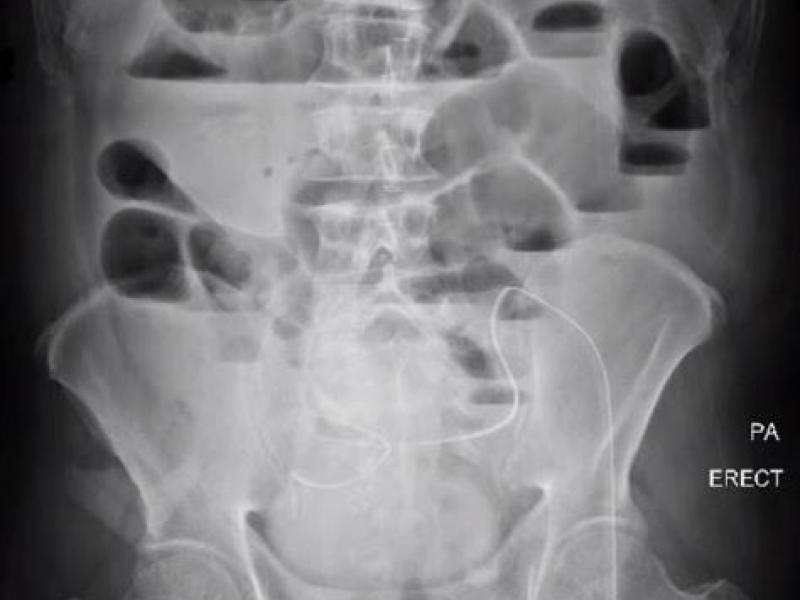

A 62 yo M presents to the ED with 1 week of abdominal